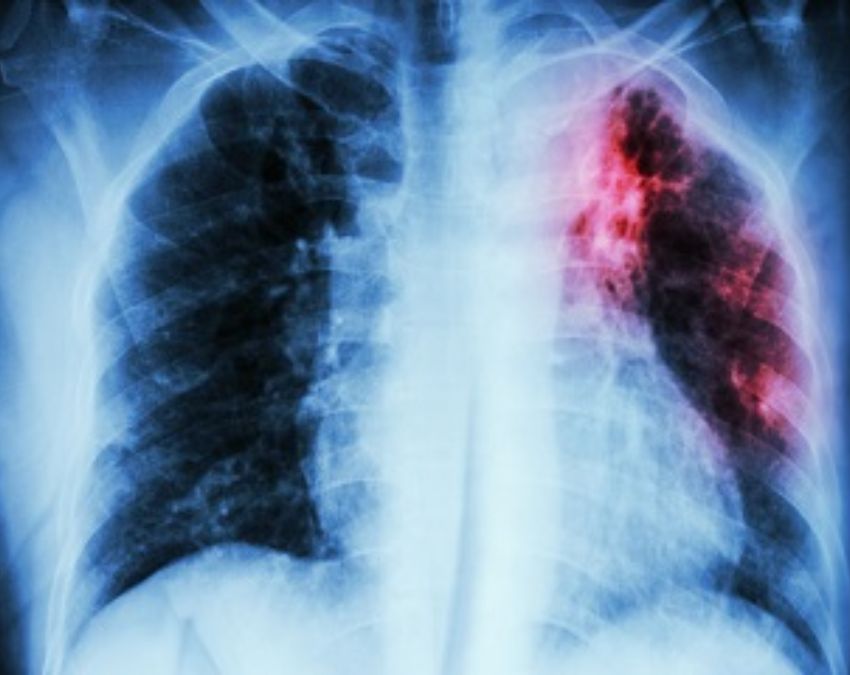

महिलाओं को खामोशी से हो रही है टीबी, शुरुआती 5 लक्षण बिल्कुल ना करें नजरअंदाज

TB Ke Lakshan: घर के कामों की वजह से अक्सर महिलाएं अपनी सेहत को नजरअंदाज कर देती हैं और कुछ बीमारियां उनके शरीर में पनपती रहती हैं. टीबी की बीमारी भी कुछ ऐसी ही है, लेकिन अगर वक्त पर इलाज किया जाए तो इसे जड़ से आसानी से खत्म किया जा सकता है.